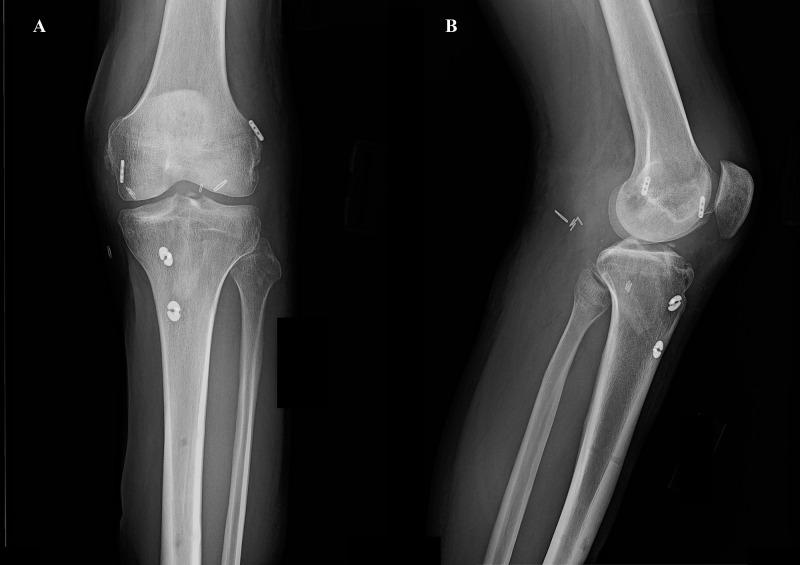

Bilateral knee dislocation is an extremely rare and devastating injury to the knee joint. This injury is a true emergency as concomitant injuries may threaten life and limb. Here, we report the case of a 26-year-old male patient who sustained bilateral knee dislocation due to a high-velocity motor vehicle accident. In this case, the patient suffered a feared complication associated with knee dislocation, popliteal artery disruption with peroneal nerve damage. Abdominal and skeletal injuries were also discovered and treated appropriately by a multidisciplinary team. A staged surgical approach to ligament reconstruction was used without any postoperative complication. Postoperatively, the patient successfully returned to his preoperative activity level.